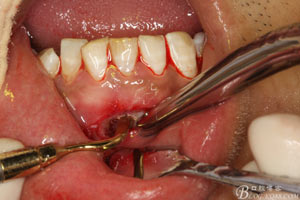

圖7.局部麻醉下,行下前牙唇側(cè)弧形切口,翻瓣可見(jiàn)31唇側(cè)骨壁有缺損,并有根充物暴露